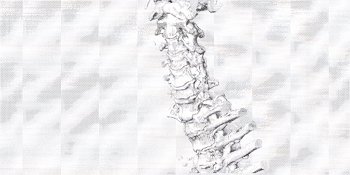

とりあえずCTスキャン。

で、頂きましたのが、その一部のこれらの画像なんです(^.-)☆

特に痛みの原因となるようなモノは見当たらず、強いて言えば『老化現象』との事でありました。